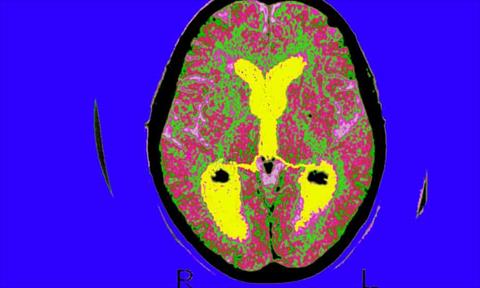

كشف باحثون في أحدث دراسة لربط صحة الأمعاء بالأمراض العصبية أن الأشخاص المصابين بمرض التهاب الأمعاء (IBD) لديهم أكثر من ضعف خطر الإصابة بالخرف.

حيث أشارت مجموعة متزايدة من الأبحاث إلى أن التغييرات في الجهاز الهضمي قد تؤثر على الدماغ من خلال الاتصال ثنائي الاتجاه المعروف باسم محور الأمعاء والدماغ.

ووجد العلماء في قت سابق، علامات على أن البروتينات غير المطوية بشكل غير طبيعي والمرتبطة بمرض باركنسون العصبي، قد تنشأ في الأمعاء وتنتقل إلى الدماغ، في حين أن التغيرات في الميكروبات المعوية يرتبط بظروف تتراوح من مشاكل الصحة العقلية لمرض الخلايا العصبية الحركية ومرض باركنسون، الذي يؤثر على الجهاز العصبي ويسبب الشلل الرعاش ونقص الحراك وتشوه المشي، ومشكلات في المخ تسبب الخرف.